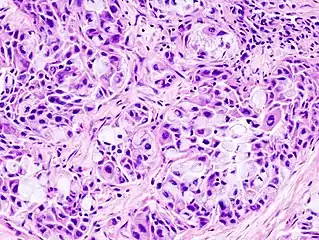

Micrograph of a mucoepidermoid carcinoma. FNA specimen. Pap stain.

In terms of diagnosis we find that histological staining, radiological imaging and molecular diagnostic features all play a role in the evaluation[1] This tumor is not encapsulated and is characterized by squamous cells, mucus-secreting cells, and intermediate cells.[7]